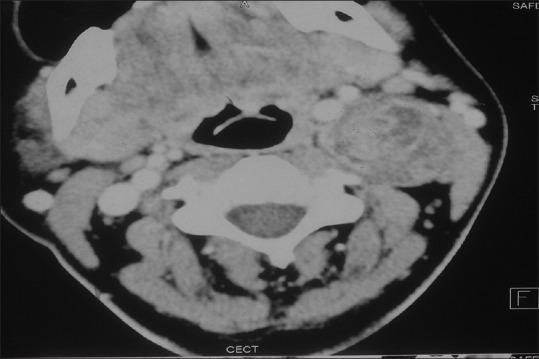

Schwannomas arising from cervical vagus nerve is an extremely rare benign neoplasm. The majority of patients present with insidiously growing lateral neck mass without neurological deficit. We report a case of symptomatic cervical vagal nerve schwannoma in a 32-year-old female. Complete surgical resection is the treatment of choice. However, anesthetic management of these tumors can be challenging. We describe here the complications experienced during the management of the patient.

起源于颈迷走神经的神经鞘瘤是一种极其罕见的良性肿瘤。大多数患者表现为隐匿性生长的颈部外侧肿块,无神经功能缺损。我们报告一例32岁女性有症状的颈迷走神经神经鞘瘤病例。完整的手术切除是首选治疗方法。然而,这些肿瘤的麻醉管理可能具有挑战性。我们在此描述该患者治疗过程中所经历的并发症。